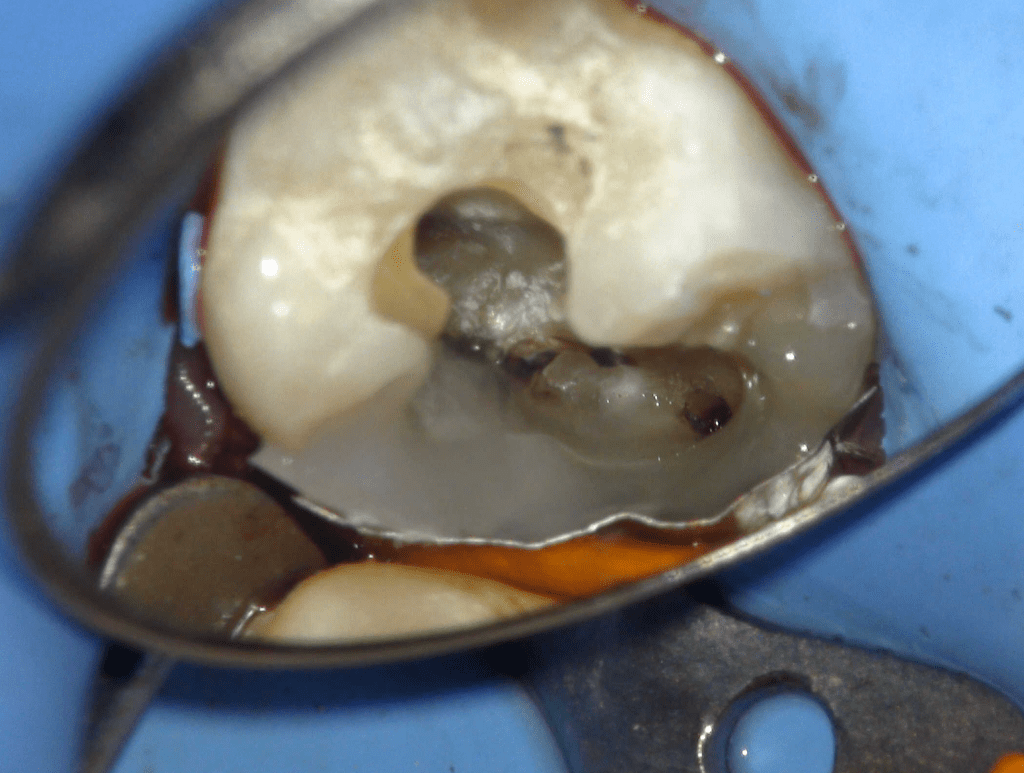

Fisura, remoción amalgama para explorar